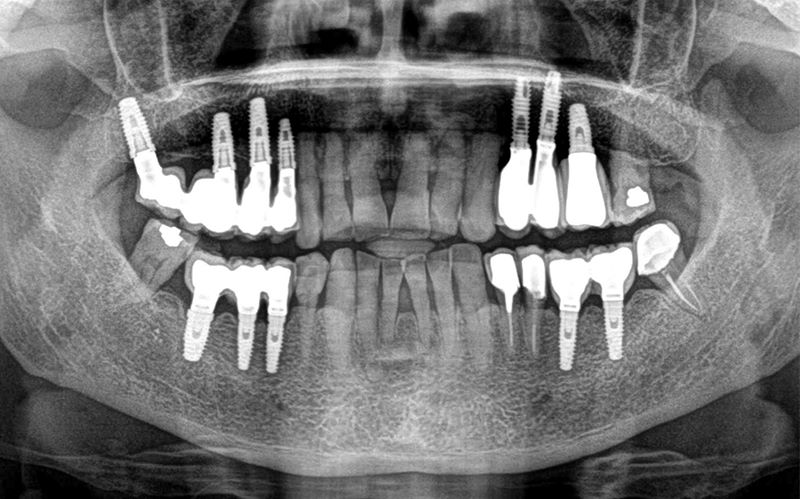

Una vez terminado cualquier tratamiento con implantes dentales es imprescindible dejar instaurado un completo plan de seguimiento y control del trabajo realizado. El control periódico permitirá la detección temprana de cualquier alteración en los tejidos blandos (encía), tejidos duros (hueso) y en los elementos que componen la prótesis implantosoportada una vez finalizado el tratamiento.

El objetivo del plan de mantenimiento de implantes dentales es identificar lo antes posible cualquier signo o síntoma que refleje una alteración que pueda poner en peligro la vida útil de los implantes dentales y, en definitiva, el funcionamiento integral de la rehabilitación mediante implantes dentales realizada.

3. Control radiográfico del implante dental y el tejido óseo.